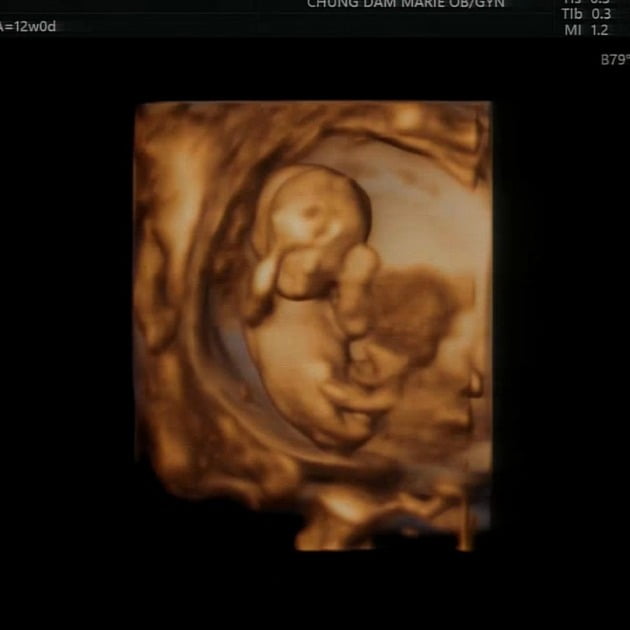

#1번사진은12주때

우리 아가 태명은 곰동이예요!

우리 곰이 동생- "곰동" 아빠가 지어줬지요

곰동이는 벌써 16주‼️